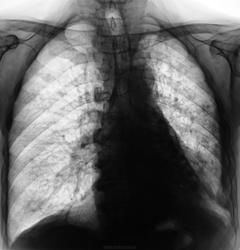

Пациент не проходил «флюшку» с 2007 года. Сегодня направлен на рентгенографию ОГК с подозрением на наличие хронического бронхита.

Уж больно тут много всего и пневмосклероз с эмфиземой и выраженной лёгочной гипертензией, и очаговые тени различной плотности, и органы средостения смещены влево  (хотя слева выраженные плевральные шварты и, вероятно, плевро-перикардиальные сращения). Справа в нижнем лёгочном поле какая-то кольцевидная тень (фиброз?, бронхоэктазы?). В такой ситуации лучше всего конечно раздобыть архив. Ну и конечно сделать томограммы, что бы убедиться что смещение средостения связано со спайками, а не с ателектазом нижней доли, а потом уже разобрать с очагами

То есть от флюшки только описание? К сожалению на томограммах не видно бронхов. А вот в проекции сердца какие участки просветления, возможно это бронхоэктазы в S10. А в остальном, наверно, очаги фиброза различной величины и формы, слева массивные плевро-апикальные и плевральные наложения ну и то, что писал раньше.

В мокроте (метод микроскопии) обнаружены "палки".

Все! Пациент отвезен в "областную туберкулёзную контору", фтизиатры признали в нем нечто родное и близкое...